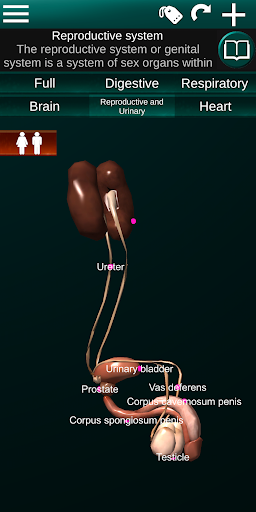

Показує 3D анатомічну модель основні органи людського тіла та опис кожного з них.

* Репродуктивна система, яка включає чоловічі та жіночі репродуктивні органи.

* Порівняйте чоловічі та жіночі органи.

* Описи кожного органу.